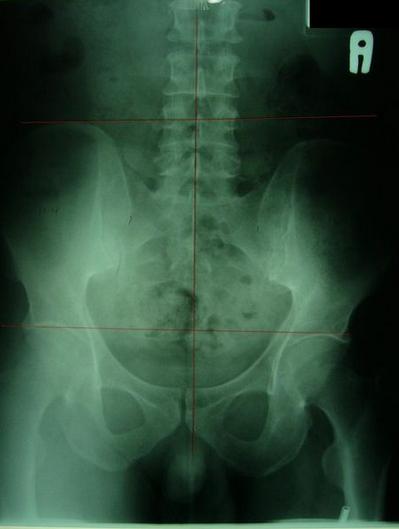

一般最常见到骨盆歪斜的案例包括产后骨盆不正、车祸、撞击、跌倒、姿势不良…等等造成。骨盆歪斜的典型症状包括腰部、髋臀部、腿、膝部疼痛。列举三个自在美国取得脊医执照以来曾经处理过骨盆歪斜相当明显的案例。都是骨盆部位曾经遭受撞击。案例A是超过十年以上的陈年车祸旧伤、另一案例B是急性摔伤(两天内)的案例。两者的X光片都依照美国脊医X摄影方式采站姿摄影评价。借此同时评价骨盆在重力(gravity)影响下的反应。也可以泯除躺歪斜摄影而造成图像不正的情况。最简单的评价要点包括骨盆高低边?中线是否穿越耻骨联合?左右两边是否对称?我简单的几条线一画,相信连外行人也可以看出明显的骨盆歪斜的情况。案例A属陈旧性伤害在调理约两个月后明显降低腰臀腿部的不舒服。而案例B属急性伤害,案例B在调理近三周后骨盆疼痛由原先的持续疼痛降低为完全不痛。之后的骨盆X光摄影重头评价也显示骨盆旋转的问题大幅改善。

案例A:右骨盆明显较低中线未穿过耻骨联合